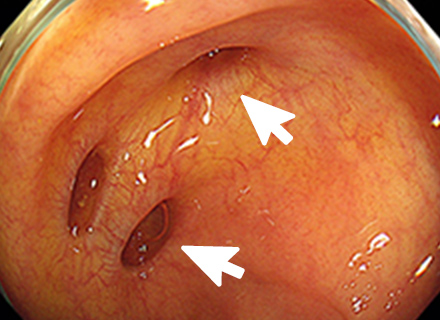

下部消化管(大腸カメラ)内視鏡検査では、肛門より太さ約13~14mmの内視鏡スコープを挿入し、空気(炭酸ガス)の注入を行いながら大腸のヒダをたぐり寄せて盲腸まで挿入します。 盲腸へ到達後、ポリープやがん、炎症などの病気がないか観察しながら内視鏡スコープを抜いてきます。 途中で病変が見つかった場合は、必要に応じて病変の一部を採取(生検)して調べたり、ポリープや早期がんなどの病変を内視鏡的に切除することもできます。検査時間は通常10~15分程度ですが、ポリープを切除すると通常より時間は長くかかります。

大腸ポリープまたは早期大腸がんの内視鏡治療